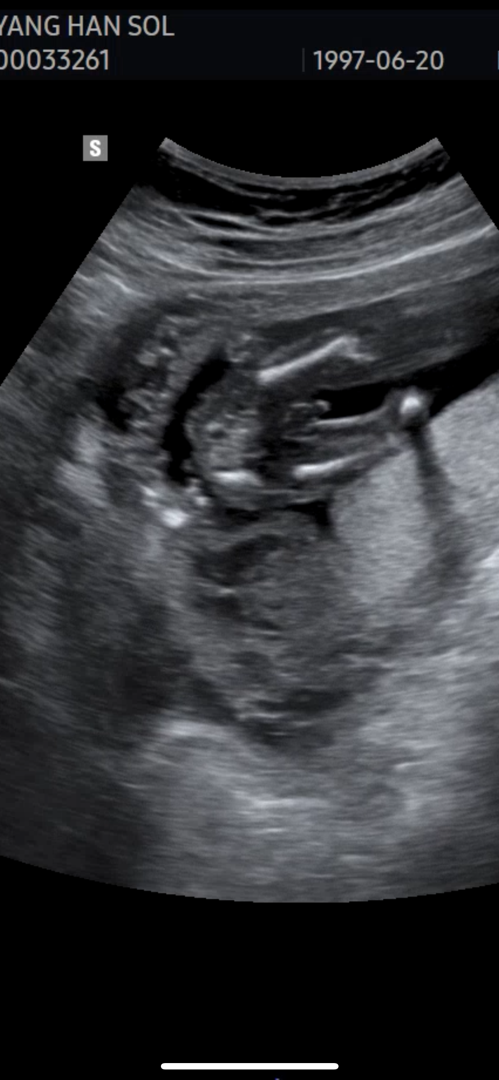

이건 그냥 아들맞는거죠,,?

사촌언니가 18주에 아들이라고 했다가 20주차에 보니까 탯줄이였던것 같다고 바껴서 딸확정받았다고 하는데 전,,, 그냥 아들 확실한거죠,,?ㅋㅋㅋㅋㅋㅋㅋㅋㅋ

빼박 ㅋ

ㅋㅋㅋㅋ그쵸,,빼박인거죠,,ㅋㅋㅋㅋㅋㅋ

답정 아들입니다 저희랑 똑같이 생겻네요 ㅋㅋ

맞아요 !! 저도 저렇게 저희 아기 아들 확인했오요 !!!

아들이요 ~~ 저도 딱 저랬어요 🙂